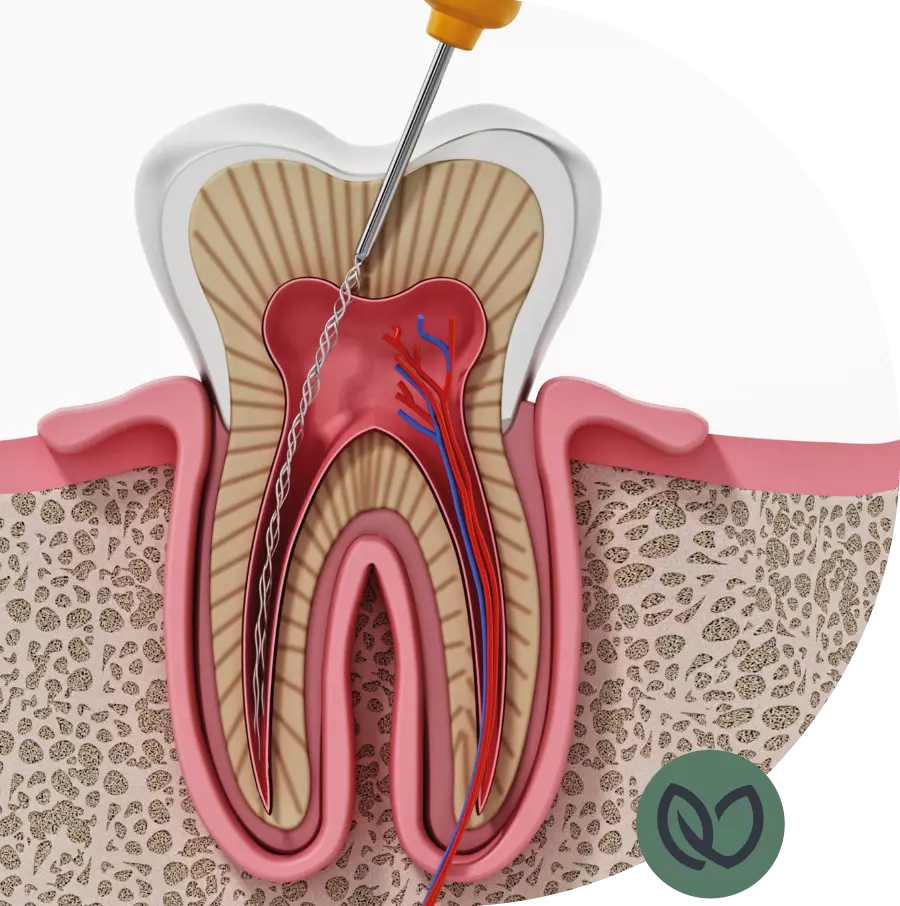

Een wortelkanaalbehandeling is meestal nodig als de tandzenuw geïnfecteerd of ontstoken raakt. Dit kan gebeuren door diepe tandbederf, een tandtrauma, een gebarsten tand of een lekkende vulling. De symptomen van een geïnfecteerde tand kunnen variëren, maar kunnen zijn: aanhoudende pijn, gevoeligheid bij het kauwen, zwelling van het tandvlees of een verkleuring van de tand.

Het aantal wortelkanalen in een tand varieert, afhankelijk van de tandlocatie. Een voortand heeft meestal één kanaal, terwijl een kies of een premolaar meerdere kanalen kan hebben. Dit is belangrijk om te weten, omdat het de complexiteit van de behandeling kan beïnvloeden. Onze ervaren tandartsen zijn goed getraind en hebben expertise in het lokaliseren en reinigen van alle kanalen, ongeacht het aantal.

Bij onze tandartspraktijk begrijpen we dat wortelkanaalbehandelingen soms als een ingrijpende procedure kunnen worden ervaren. Onze ervaren tandartsen zullen uw tand grondig beoordelen en, indien nodig, een wortelkanaalbehandeling aanbevelen. We zullen de procedure stap voor stap met u bespreken en eventuele vragen of zorgen die u heeft beantwoorden. Tijdens de behandeling zorgen we ervoor dat u zo comfortabel mogelijk bent door gebruik te maken van moderne verdovingsmethoden en technieken.